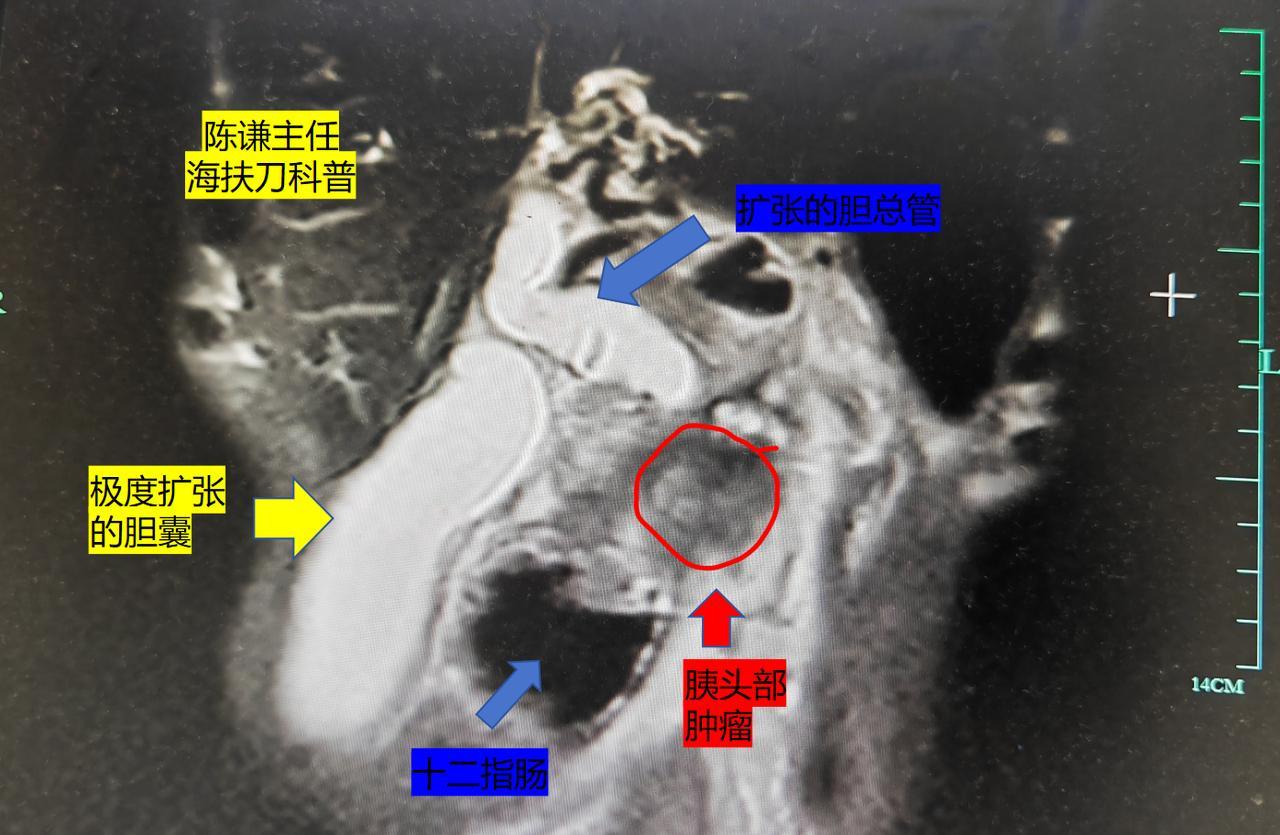

胰腺癌是临床中非常棘手的恶性肿瘤,不仅仅肿瘤恶性程度高,并且对放化疗不敏感,并且肿瘤位置一般都是靠近血管,肠道,即使能手术也存在手术创伤大,恢复慢,并发症多等问题。那对于晚期胰腺癌难道我们医生就真的束手无措了吗? 这是我们一个半月治疗的一名晚期胰腺癌,肿瘤位于胰头部压迫胆总管,患者已经出现胆囊的极度扩张,病人肿瘤紧贴腹主动脉,靠近胃肠道,患者也无法耐受传统的手术治疗。 病人家属是一名外科医生,在了解到海扶刀治疗可以无创治疗晚期胰腺癌后,至我们中心就诊,经过海扶刀治疗后一个月,患者在当地复查,肿瘤已经坏死缩小几乎看不到了,同时患者胆道压迫也得到了缓解,胆囊也缩小了,胆管梗阻症状也改善了。 晚期胰腺癌虽然总体预后不佳,但是选对治疗方法,也可能取得良好的效果,提高生活质量。海扶刀 陈谦医生海扶刀治疗病例集